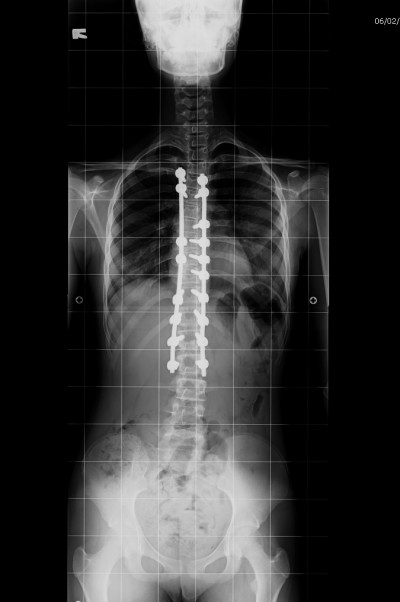

Korse tedavisine yanıt alınamadığı durumlarda cerrahi tedaviye başvurulur. Cerrahi tedavi büyümesi devam eden ve büyümesi tamamlanmış hastalarda farklılık ihtiva eder. Büyümesi tamamlanmamış çocuklarda büyüme dostu implantlar (uzayan rod, magnetik rod, bantlama yöntemi vs.) kullanılır. Büyümesi tamamlanmış çocuklarda ise en sık yapılan cerrahi işlem sırttan vida ve çubuklar kullanılarak enstrümentasyon ve kemik greftiyle yapılan füzyondur. Modern enstrüman sistemleri ile eğriliği %80 oranında düzeltmek mümkündür.